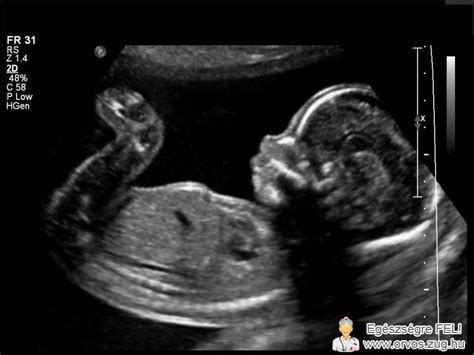

A diagnosztika az elmúlt évtizedekben jelentősen fejlődött. Míg korábban a méhnyak-terhességet gyakran csak műtét során ismerték fel, ma a korai terhességi ultrahangvizsgálat kulcsszerepet játszik a felismerésben. A transzvaginális ultrahang lehetővé teszi, hogy az orvos pontosan lássa a petezsák elhelyezkedését. Cervikális graviditás esetén a terhességi zsák a méhnyakcsatornában helyezkedik el, a méh ürege üres, a belső méhszáj zárt, és jellegzetes „homokóra” alak figyelhető meg.

A korszerű Doppler-ultrahang vizsgálat kimutathatja a trophoblast fokozott keringését is, ami segít elkülönítani az állapotot egy vetélés során a méhnyakba csúszó terhességi szövettől. A laboratóriumi vizsgálatok közül a szérum béta-hCG szint követése fontos szerepet játszik. A diagnózis felállítása után rendszeres kontroll szükséges, hogy megbizonyosodjanak a hormonszint csökkenéséről.